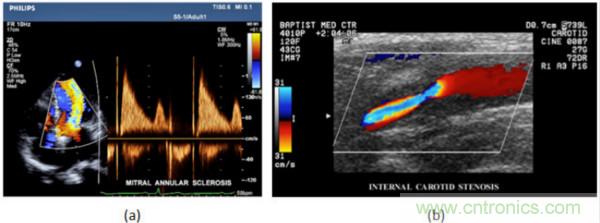

在CW和PW多普勒模式中,流信息是從一個聚焦聲束中獲得的,類似于A模式成像。在20世紀80年代,研究人員基于彩色多普勒技術(shù)完成了血流分布的二維信息可視化。彩色多普勒處理也是基于B模式/PW模式信號路徑。從感興趣區(qū)域收集多幀RF數(shù)據(jù)。由于感興趣區(qū)域中的血液流動導(dǎo)致圖像幀之間存在數(shù)據(jù)差異。相域中的自相關(guān)和時域中的互相關(guān)兩種算法可從RF數(shù)據(jù)中提取數(shù)據(jù)方差(即血流速度和方向信息):。根據(jù)預(yù)定義的顏色漸變條相應(yīng)地映射包括速度和方向的血流信息。通常,藍色和紅色代碼分別識別朝向和遠離換能器移動的血流。當流速增加時使用更亮的顏色,反之亦然。顏色映射的2D分布始終疊加在B模式圖像上,以實時同時顯示個體解剖結(jié)構(gòu)和血流。它對于診斷心血管疾病,如血管閉塞和心臟瓣膜反流,極其有用。典型的彩色多普勒圖像如下圖所示,(b)顯示頸動脈狹窄引起的血流流速變化。

圖7.彩色多普勒成像:(a)以彩色多普勒和CW模式獲得的圖像(由Philips提供); (b)顯示頸動脈狹窄的彩色多普勒(由GE提供)